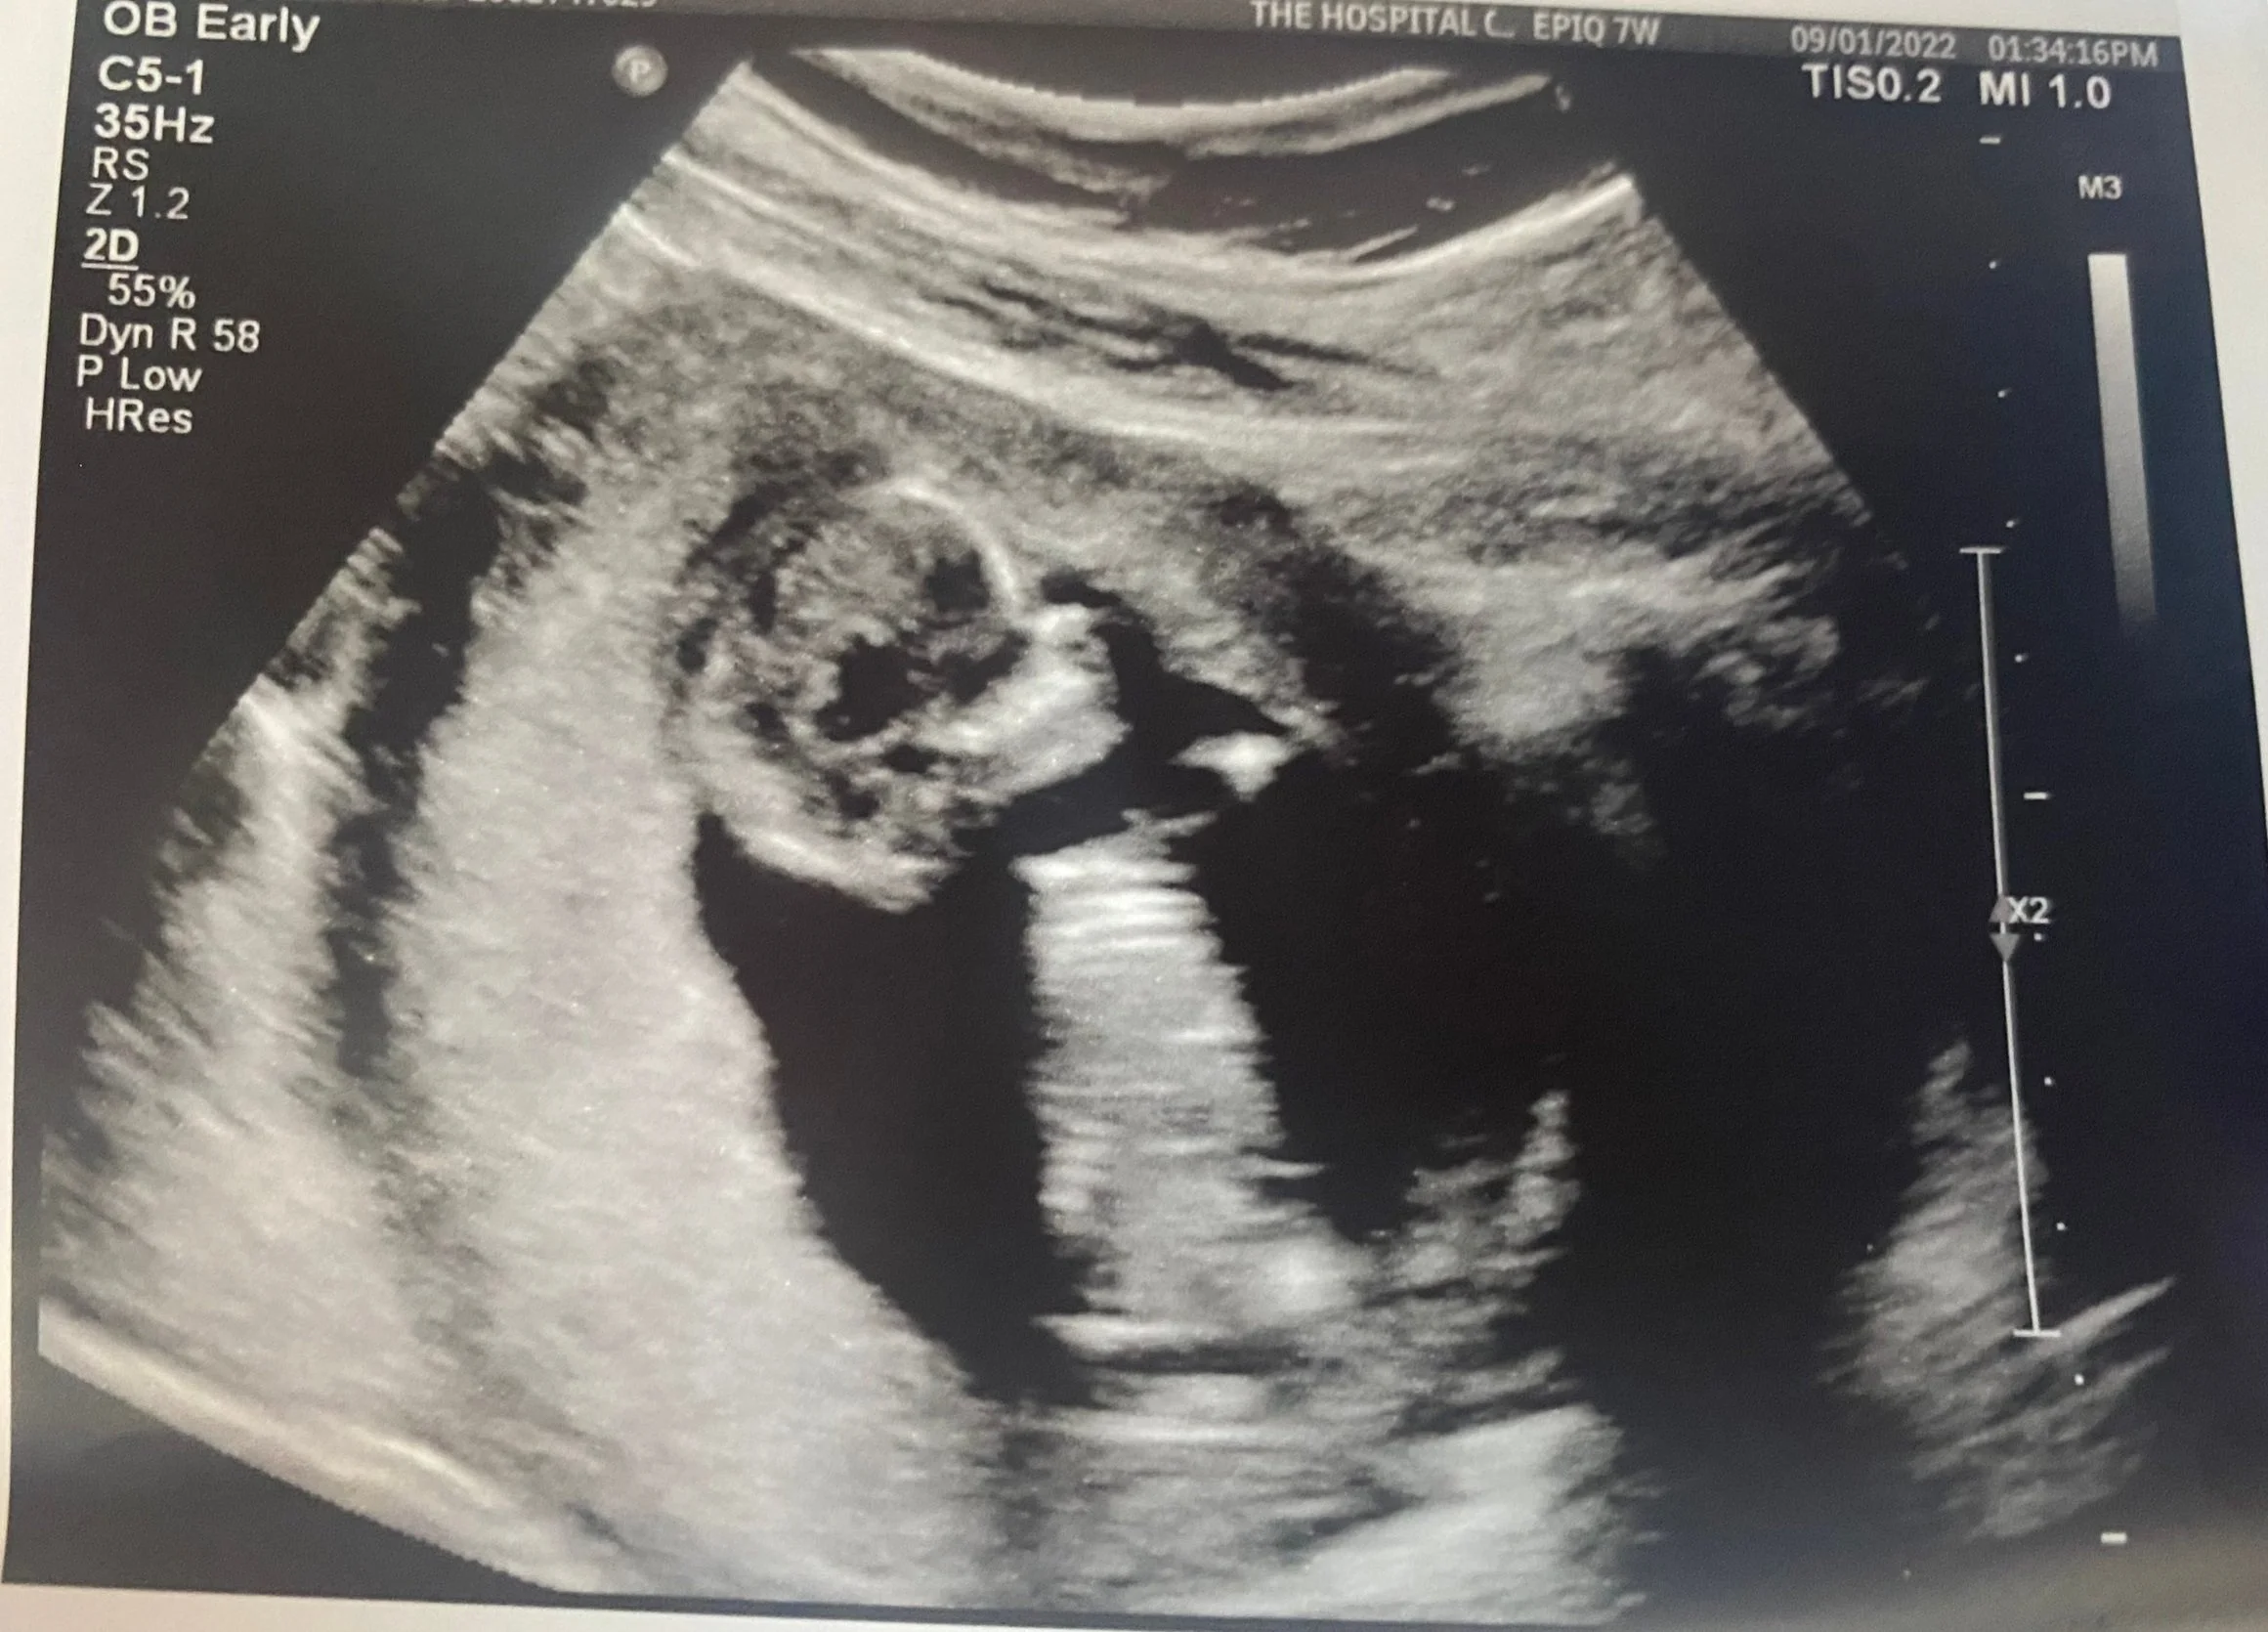

I’m 7 Weeks Pregnant????

Let me first start of by saying that I did not know that I was pregnant until week 7 of pregnancy. I had had a very busy travel summer kicking things off with a beautiful wedding in Maryland. I had the time of a my life indulging in West African culture at my friend Yinka’s wedding (who also happens to be thriving in this influencer space). I remember arriving late to her traditional wedding from CT and one of the issues having been getting my cycle on arrival to our hotel in Maryland. That my friend’s was June 3rd, 2022. Everything else that came after that, was certainly a blur.

My beautiful surprise.